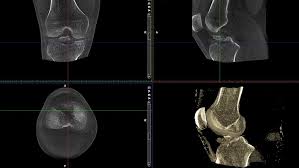

Bei der digitalen Volumentomographie werden innerhalb von wenigen Sekunden 3-dimensionale Röntgenaufnahmen von den Gelenken der Arme und Beine sowie vom Kopf durchgeführt. Hierzu befindet sich der Patient in einer angenehmen Position.

- DVT-Aufnahme eines Kniegelenkes

Aufgrund der Technik ist die digitale Volumentomographie auch in der Lage bei Endoprothesenlockerung oder -infekt den Übergang der Endoprothese zum Knochen (das sogenannte Interface) exakt darzustellen und ist somit der CT und der MRT in ihrer Aussage bei Weitem überlegen.